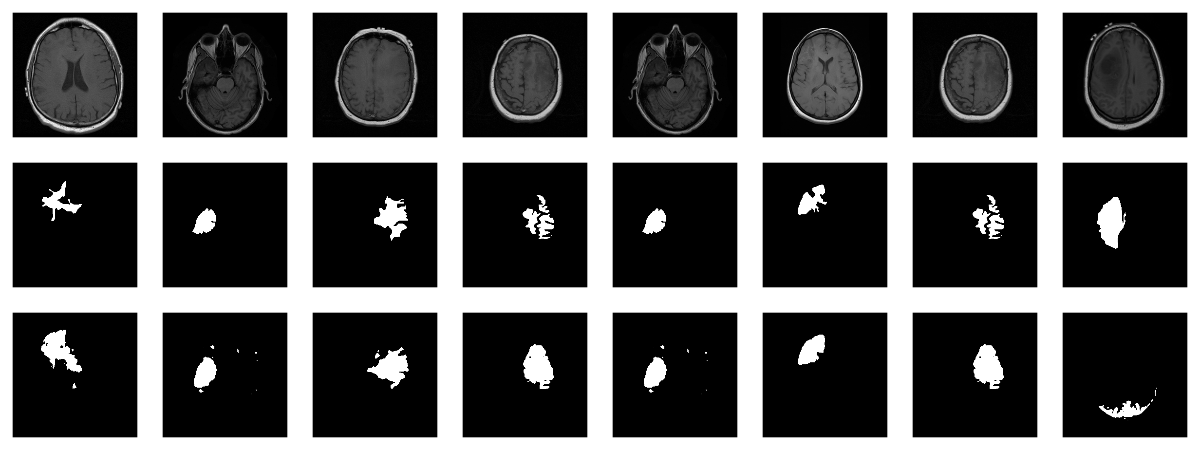

Now, since we don’t have a separate test set, we already know the average out-of-sample metrics; but in the end, what we care about are the generated masks. Let’s view some, displaying ground truth and MRI scans for comparison.

We also print the individual cross entropy and dice losses; relating those to the generated masks might yield useful information for model tuning.

Sample 1, bce: 0.088406, dice: 0.387786}

Sample 2, bce: 0.026839, dice: 0.205724

Sample 3, bce: 0.042575, dice: 0.187884

Sample 4, bce: 0.094989, dice: 0.273895

Sample 5, bce: 0.026839, dice: 0.205724

Sample 6, bce: 0.020917, dice: 0.139484

Sample 7, bce: 0.094989, dice: 0.273895

Sample 8, bce: 2.310956, dice: 0.999824

While far from perfect, most of these masks aren’t that bad – a nice result given the small dataset!